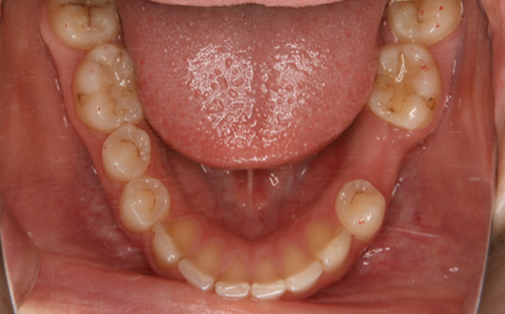

Before

左上の親知らずの歯を移植しました。20代前半の症例です。

ご自身の歯のため親和性が高く、移植後も不自由なく機能しています。